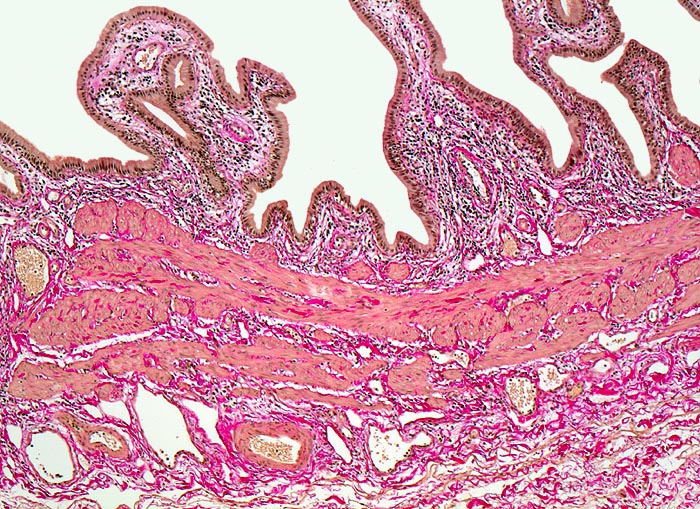

PathoPic ID 3213 - Normale Gallenblase

Normale Gallenblase

Normalbefund

Gallenblase

Leber, Gallenwege, Pankreas

Die Gallenblasenschleimhaut bildet unregelmässige

Falten, die bedeckt sind von einem

hochzylindrischen Epithel. Auf die Mukosa folgt eine Schicht mit

glatter Muskulatur. Am unteren Bildrand das Bindegewebe der

subserösen Schicht.

Histologie

50